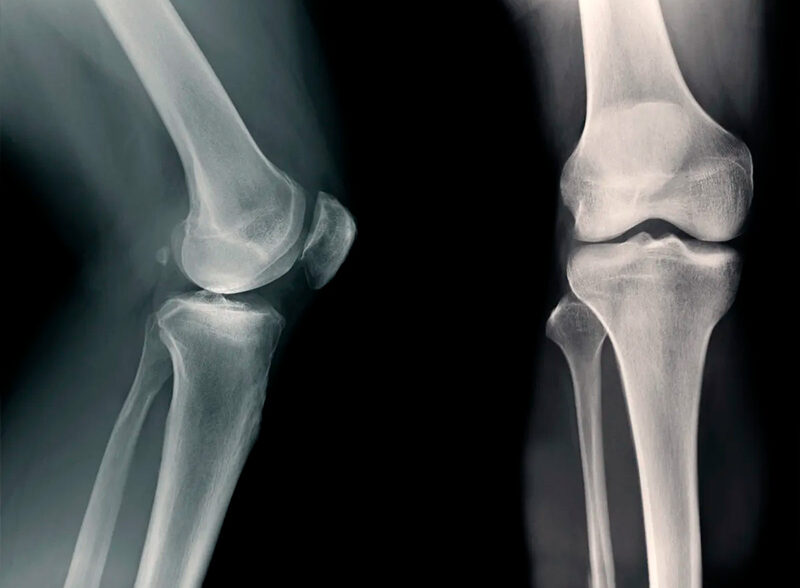

Остеоартроз — одне з найпоширеніших захворювань суглобів, яким страждають мільйони людей у всьому світі. Це хронічне дегенеративне захворювання, при якому руйнується хрящова тканина, стоншуються суглобові поверхні, а рухи стають болючими та обмеженими.

Найчастіше остеоартроз уражає колінні й кульшові суглоби, рідше — плечові, гомілковостопні, міжфалангові суглоби кистей і хребет.